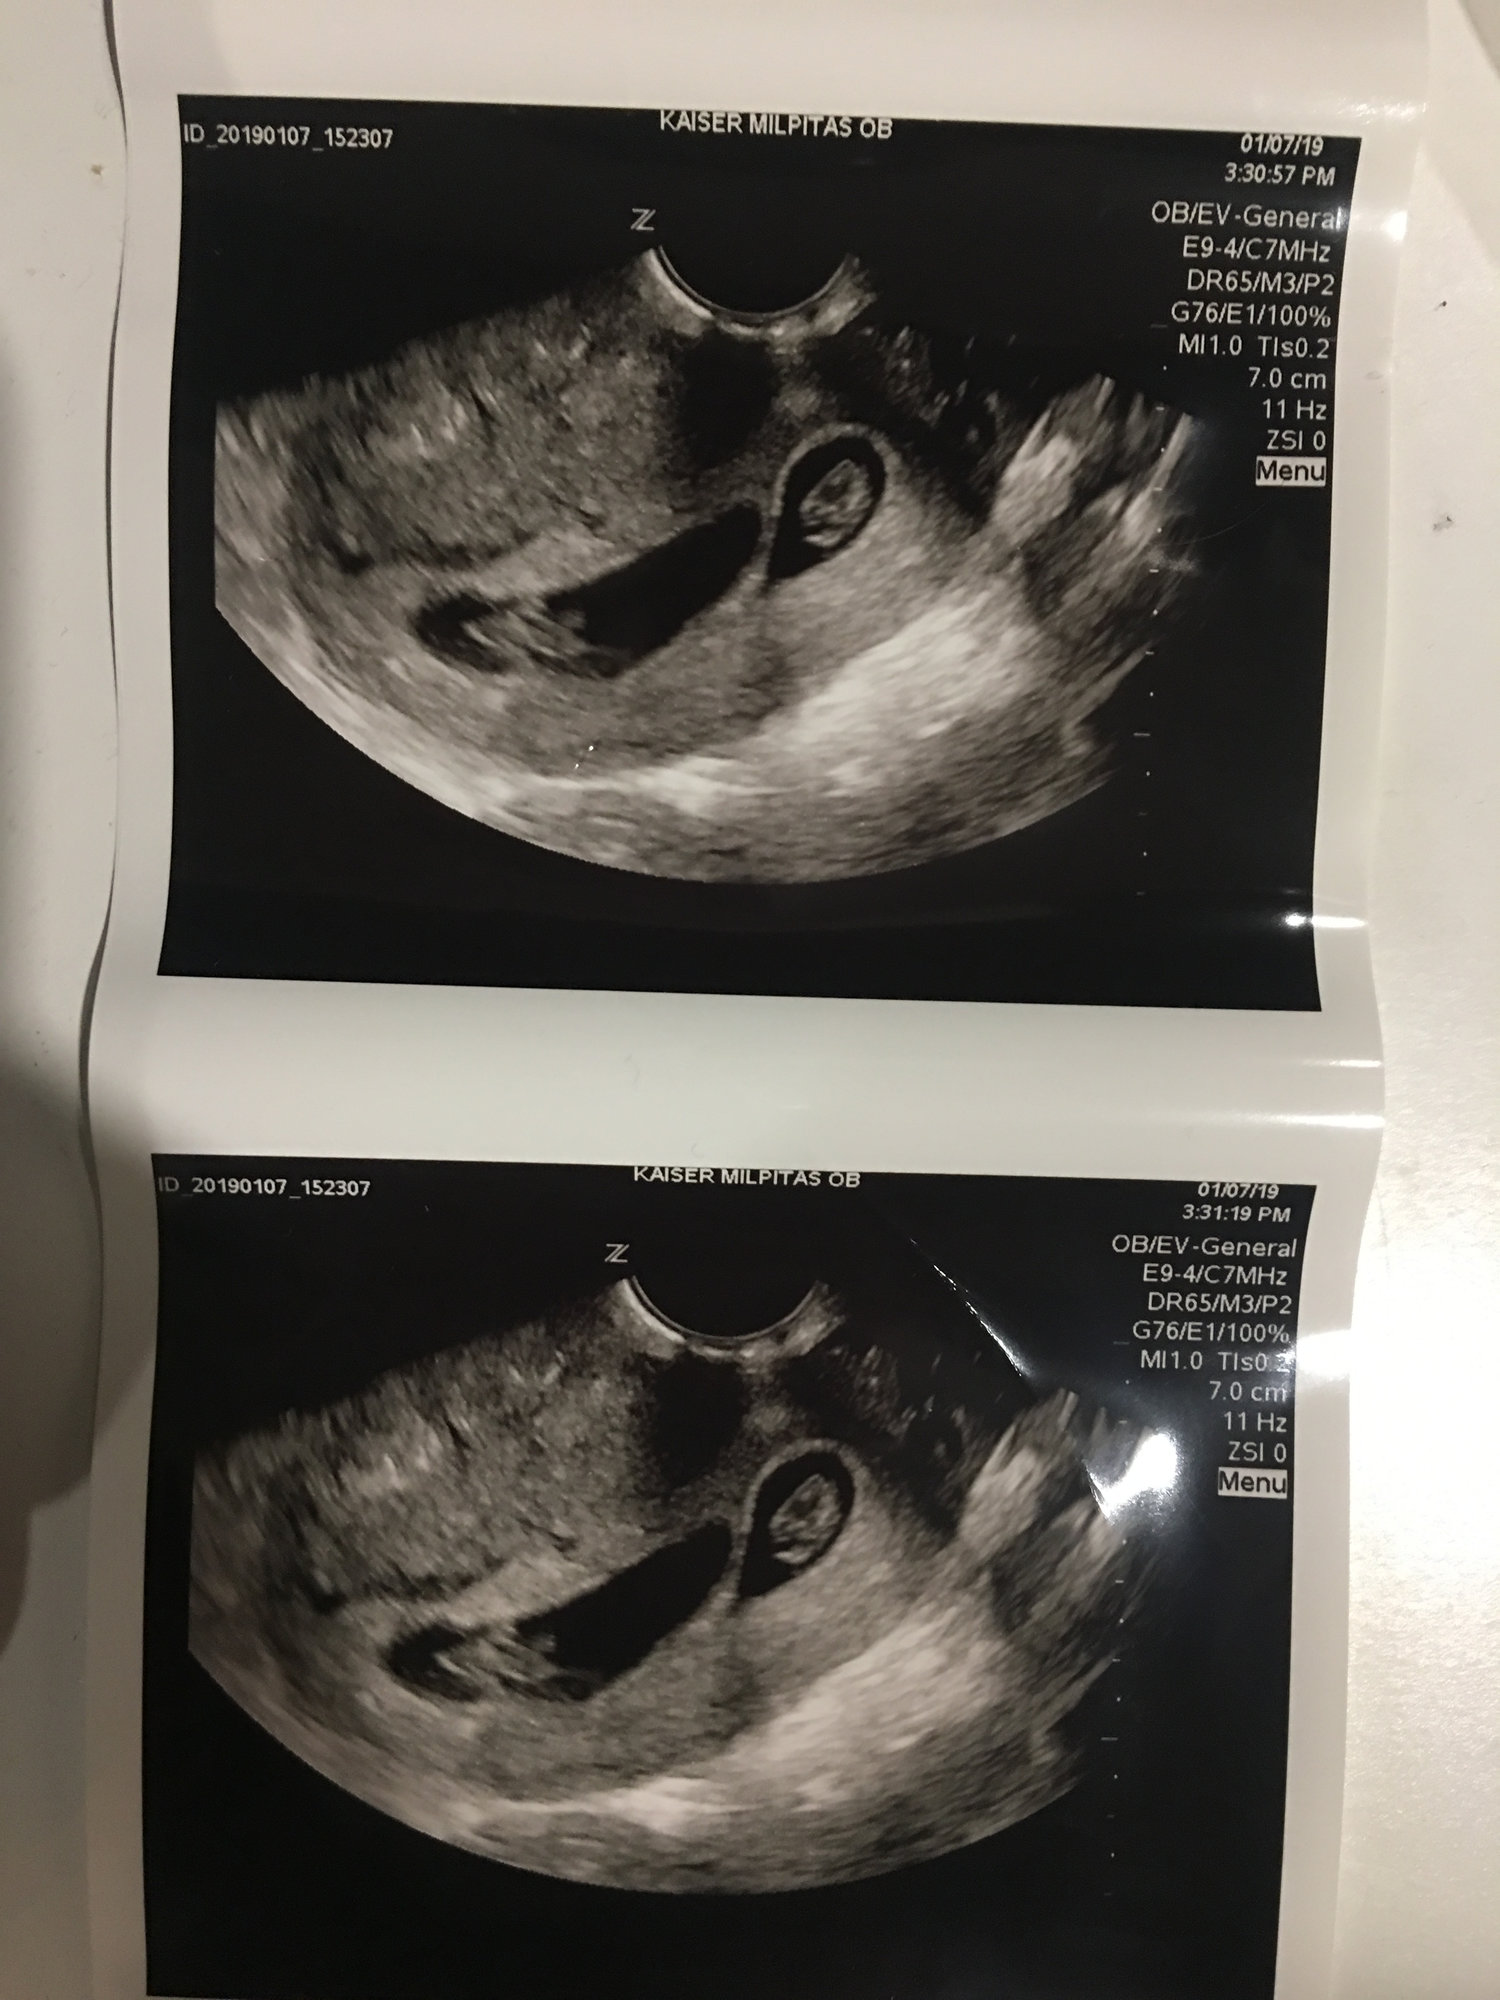

Such a wonderful surprise to see not 1 but 2 nuggets measuring in at 9W/6D with HR of 172 and 9W/3D with HR of 170. Thankful that all is well